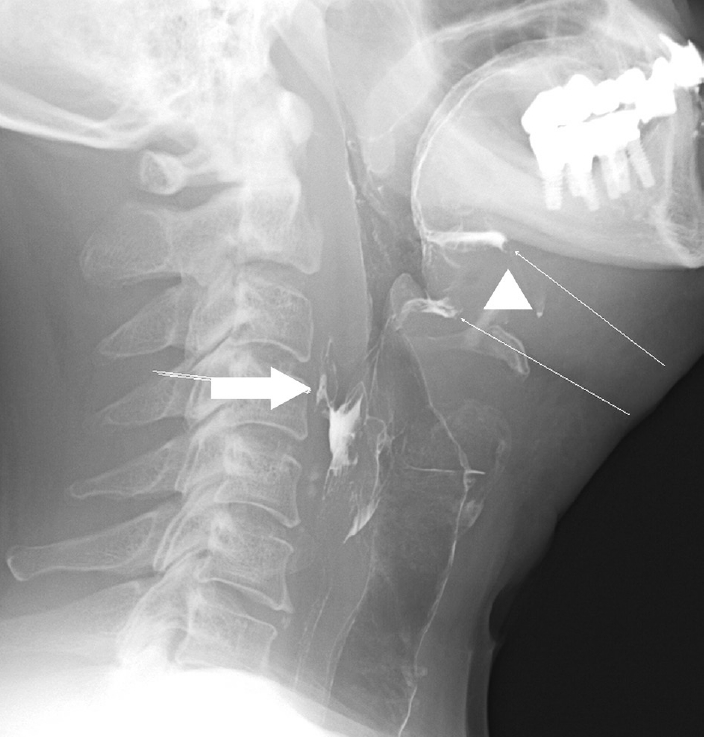

퇴원 후 3일째 외래 추적 관찰 중, 이전의 경부 level II 피부누공 위치보다 상방에 새로운 누공 입구가 발생한 것을 확인하여 국소마취하 절개 배농술 시행 후 배액관을 삽입하였고, 경구식이는 유지하며 압박드레싱을 시행하여 배농술을 시행한지 6주 후에 누공 입구가 막힌 것을 확인하였다(Fig. 8). 누공 입구가 막힌 뒤 외래 추적 관찰 중 2주째, 동일 부위에 인두피부누공이 재발하여 외래에서 국소마취하 절개 배농술을 다시 시행하였고, 압박드레싱을 시행한 후 5주째 누공이 완전히 막혀 치료를 종료하였다. 치료 종료 후 2주째 시행한 경부전산화단층촬영 검사상 구인두에서 후인두공간으로 이어지는 누공과 좌측 구인두에서 좌측 악하공간으로 이어지는 누공이 사라진 상태가 확인되었다(Fig. 9). 이후 13주까지 추가 누공 발생 없이 잘 막힌 상태로 유지하며 경과 관찰 중이다.

환자는 술후 동시항암방사선 치료 종료 6주 후부터 호흡곤란 증상을 호소하여 방사선으로 인한 후두염 진단하에 3차례 입원 후 보존적인 치료를 하고 퇴원하였다. 이후 정기적 외래 추적 관찰 중 술후 동시항암방사선 치료 종료 후 21주째, 좌측 경부 level II에 작은 피부 결손 부위와 함께 혼탁성삼출물이 흘러나오는 것을 발견하였고, 당시 시행한 경부 전산화단층촬영 검사에서, 이전에는 보이지 않던 좌측 편도와에서 좌측 부인두공간으로 연결된 누공이 새로 형성된 것을 확인하였다(Fig. 3). 이에 따라 국소마취하 절개 배농술을 시행한 뒤, 피부 결손 부위에서 구인두 공간까지 이어지는 누공길(fistulous tract)을 확인한 이후, 배액관의 도관을 재단하고 경부에서 구인두 방향으로 이를 거치하여 지속적 음압 드레싱을 시행하였고, 이와 함께 비영양관 튜브를 통한 식사 및 정맥 내 항생제 치료를 시행하였다(Fig. 4). 치료를 유지하여 1달 뒤 시행한 경부 전산화단층촬영 검사에서 인두피부누공이 호전되지 않은 것을 확인하였고, 이에 따라 전신마취하 대흉근피판을 이용하여 결손 부위를 재건하였다(Fig. 5). 수술후 8일째 금식과 정맥 내 고영양 치료를 유지하던 중, 환자가 협조하지 않아 소량의 경구식이를 시작하였다. 수술 후 12일째 수술 부위 배액관을 통해 다시 타액이 유출되는 것을 확인하여 전신마취하에 경부 탐색술을 시행하였고, 피판 부위는 유지되고 있는 것을 확인하여 죽은조직제거술을 시행한 후 수술을 종료하였다. 환자는 금식을 다시 유지하였고 대흉근 피판재건술 이후 38일째 식도조영술을 시행하였으며, 좌측 이상와 부위에서 작은 누공이 추가로 확인되었으나(Fig. 6), 환자가 경구식이를 강하게 희망하여 2일 후 소량의 경구식이를 재개하였다. 이후 배액관의 배액량이 줄어드는 양상을 보이는데다 환자가 외래 통원치료를 희망하여 입원한 후 80일만에 배액관을 유지한 채로 퇴원하였다.